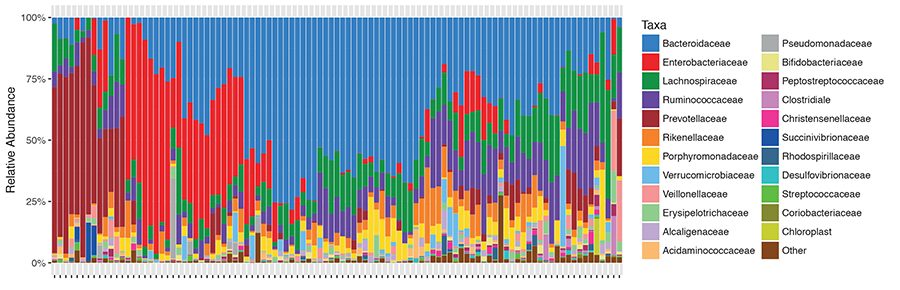

Dr. Eduardo Vilar-Sánchez,博士,Dr. Prevención Clínica del Cáncer y Oncología Médica胃肠道,analizaron la expresión genética para caracterizar el perfil inmunológico en 11 pólipos在síndrome de Lynch的14名患者的早期肿瘤。Como对照,研究分析17 pólipos常见腺瘤性poliposis adenomatosa (FAP)患者的前恶性肿瘤,síndrome de cáncer结肠遗传,无MMR缺陷。

结果:revelaron una expresión significativamente más alta de varios marcadores de activación inmunológica-que incluyen células T CD4阳性,moléculas proinflamatoras y proteínas de puntos de control tales como PD-L1 y LAG3-en pólipos de síndrome de Lynch que en pólipos de FAP。禁运,相反地,在activación inmunológica的传统的los modelos tradicionales, los perfiles inmunológicos en los pólipos de síndrome。

“新的结果没有符号,模型estándar。”“mayoría恶性前病变在neoantígenos中没有发生过多的变异”,我是医生Vilar-Sánchez。“罪恶的禁运,你存在activación inmunológica,你的意思是在activación之前发生变异”。